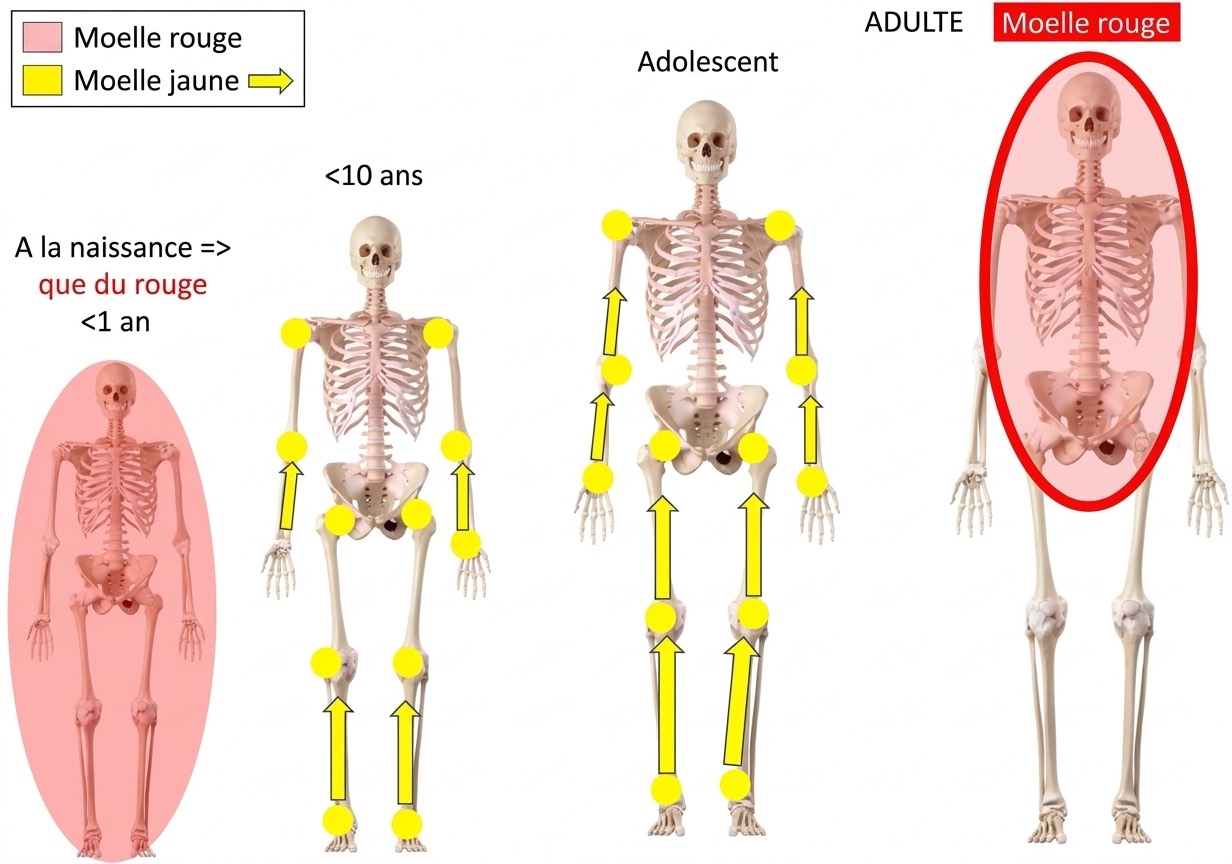

aspect normal moelle jaune (graisse) = HT1 avec ilôts de moelle rouge (hématopoïétique) = hT1

aspect normal moelle jaune (graisse) = HT1 avec ilôts de moelle rouge (hématopoïétique) = hT1

apparition progressive moelle jaune dans les membres = épiphyses > diaphyses > métaphyses

apparition progressive moelle jaune dans les membres = épiphyses > diaphyses > métaphyses

Modifications

- ↗ moelle jaune = fracture ancienne, discopathie Modic 3, radiothérapie

- ↗ moelle rouge (épargne les apophyses et épiphyses) = sportif, fumeur, obèse, anémie, G-CSF

reconversion médullaire = ilôts hT1 avec faible rehaussement

reconversion médullaire = ilôts hT1 avec faible rehaussement

moelle en hT1 par rapport au disque et HSTIR par rapport aux muscles

moelle en hT1 par rapport au disque et HSTIR par rapport aux muscles

=> à confronter au bilan biologique avec électrophorèse des protéines sériques